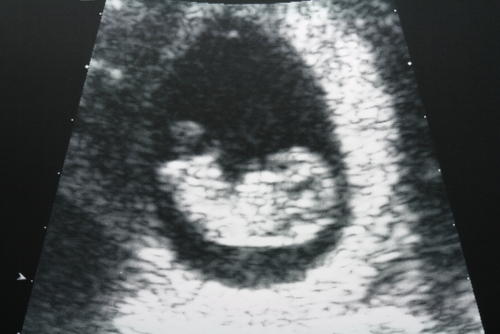

一度流産を経験しているママであれば、さらに強く不安を感じてしまうことでしょう。特に出血や痛みといった自覚症状がないまま起こる稽留流産後のママにとっては、赤ちゃんを包んでいる袋の「胎のう」が確認できるか、次は心拍確認ができるかと、病院での健診のたびに不安に押しつぶされそうになるかもしれません。